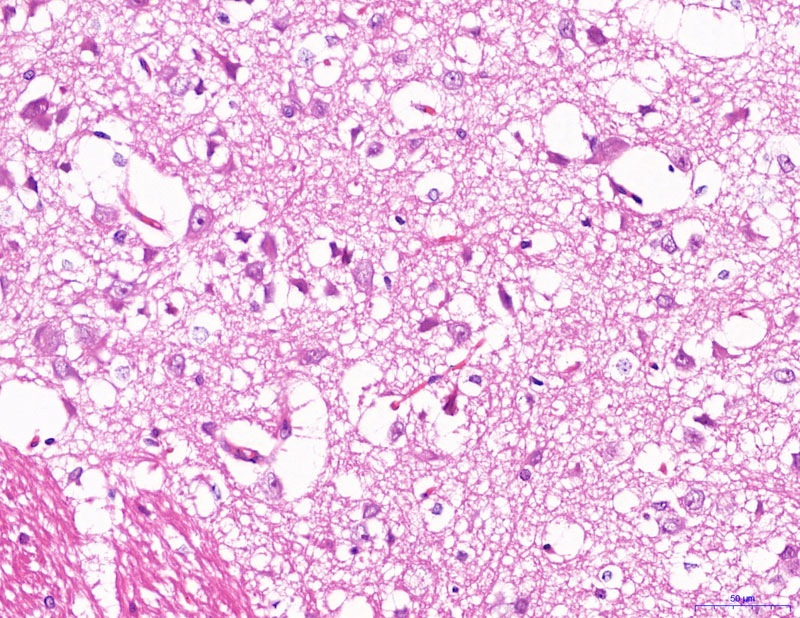

HE染色【組織病理染色】

模型-400